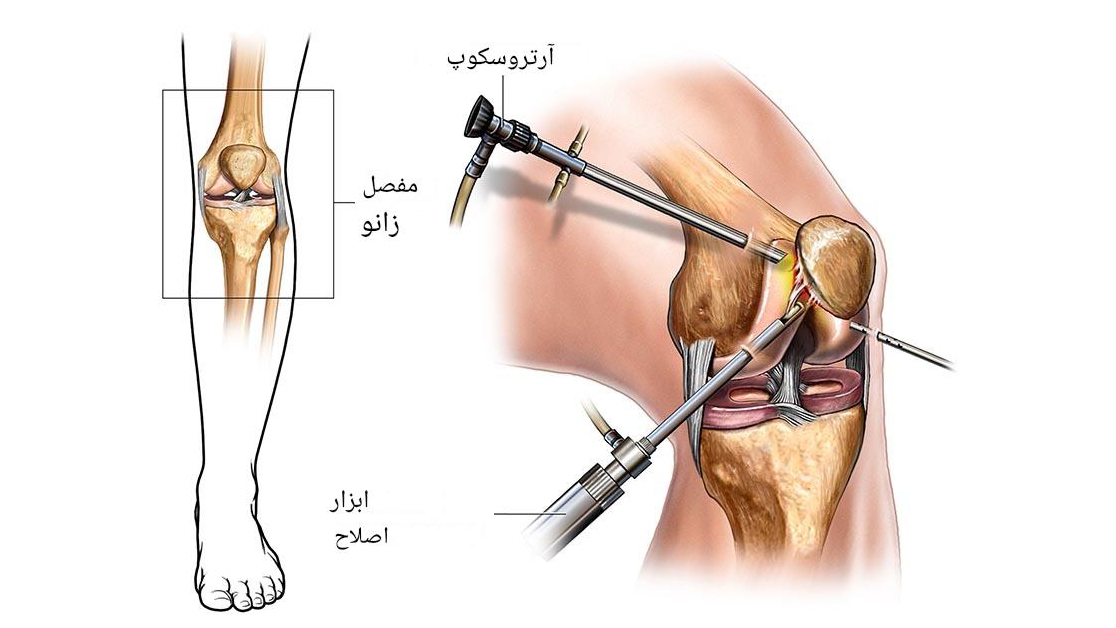

2. درمان جراحی

در صورت وجود آسیب شدید مانند پارگی رباط یا ناپایداری شدید، جراحی توصیه میشود:

- جراحی باز یا آرتروسکوپی

- بازسازی رباط صلیبی

- اصلاح مشکلات کشکک زانو

- تعویض مفصل در موارد پیشرفته آرتروز

زمانی که آسیبهای ساختاری شدید مانند پارگی رباطها، بیثباتی قابلتوجه مفصل پیشرفته وجود داشته باشد، درمان جراحی بهترین گزینه محسوب میشود. جراحی ممکن است بهصورت آرتروسکوپی (کمتهاجمی) یا جراحی باز انجام شود تا ساختارهای آسیبدیده ترمیم یا بازسازی شوند. بازسازی رباط صلیبی به بازگرداندن ثبات زانو کمک کرده و اصلاح مشکلات کشکک باعث بهبود حرکت طبیعی مفصل میشود. در موارد پیشرفته که مفصل بهشدت تخریب شده است، تعویض مفصل زانو میتواند درد را کاهش داده و توانایی حرکت بیمار را بهطور قابلتوجهی بازیابی کند.